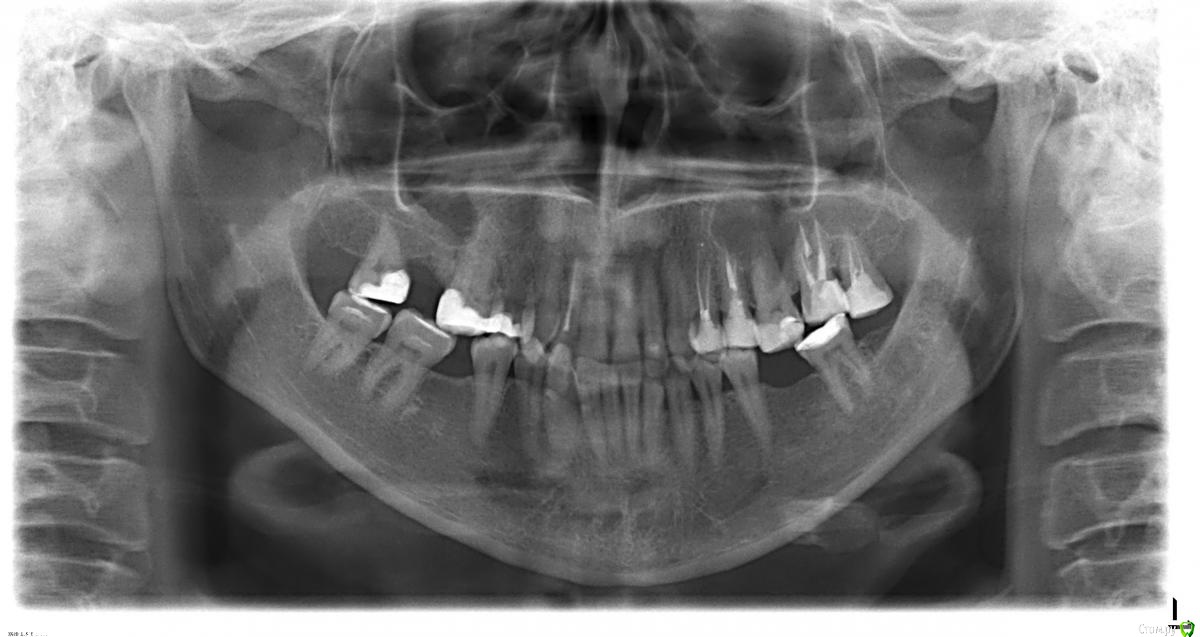

c2406 Опубликовано 29 октября, 2016 Поделиться Опубликовано 29 октября, 2016 Здравствуйте. Прошу помочь понять и оценить масштабы необходимого лечения. Месяц назад занялась зубами. В планах вылечить что можно и поставить импланты там, где зубы отсутствуют. На данный момент вылечено 2 зуба (пульпит). Проведена консультация с имплантологом, возможна установка 2-х имплантов (верхний с закрытым синуслифтингом). Терапевт и имплантолог между собой не связаны, я живу в небольшом городке, тут провожу только лечение.Есть ли у меня зубы, на которые стоит обратить первоочередное внимание или перелечить? Жалобы перед началом лечения у меня были только на 1 зуб - верхняя полуразвалившаяся 7-ка (2.7?), её залечили. Второй вылеченный зуб (верхняя 2-ка, 1.2?) не беспокоил, даже не подозревала что там проблемы. Со слов терапевта, осталось лечить только кариес разной степени. Но снимок в клинике не делали, тот что я прикладываю я делала для консультации с имплантологом. Очень хочется сделать всё по максимуму, пока есть такая возможность.Заранее большое спасибо откликнувшимся (изображение по ссылке увеличивается по клику). http://images.vfl.ru/ii/1477754283/9ea96e4a/14723320_s.jpg Ссылка на комментарий

DmitrySH Опубликовано 29 октября, 2016 Поделиться Опубликовано 29 октября, 2016 18, 47 сдвинулись к центру16,26 вниз + снижение высоты из-за обширных пломб. Ссылка на комментарий